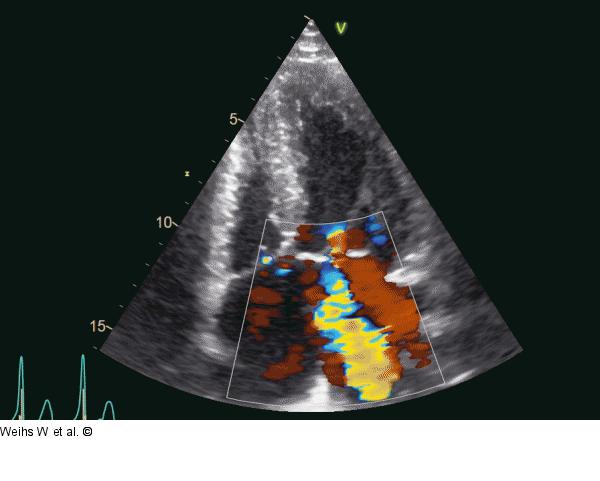

Abbildung 4: Vierkammerblick Darstellung der Mitralinsuffizienz im Vierkammerblick |

Abbildung 4: Vierkammerblick

Darstellung der Mitralinsuffizienz im Vierkammerblick |